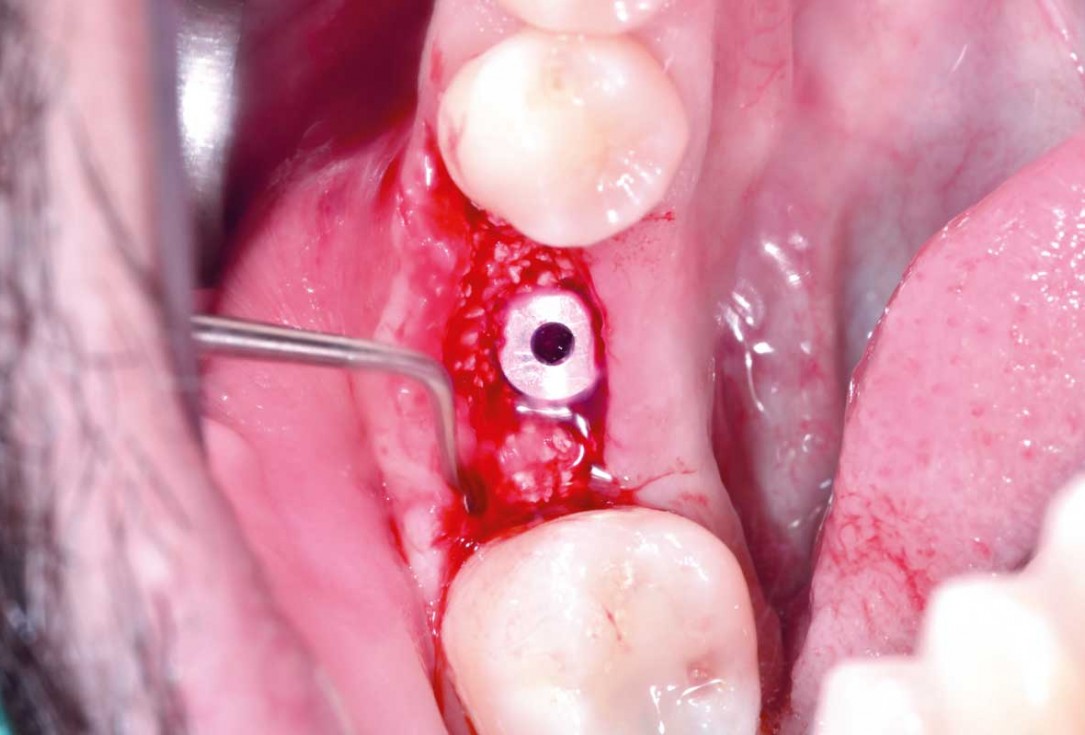

03/25 - Situation after tooth extraction and implant placementImmediate implant placement and peri-implant bone augmentation with cerabone® plus - Dr. R. Block Veras